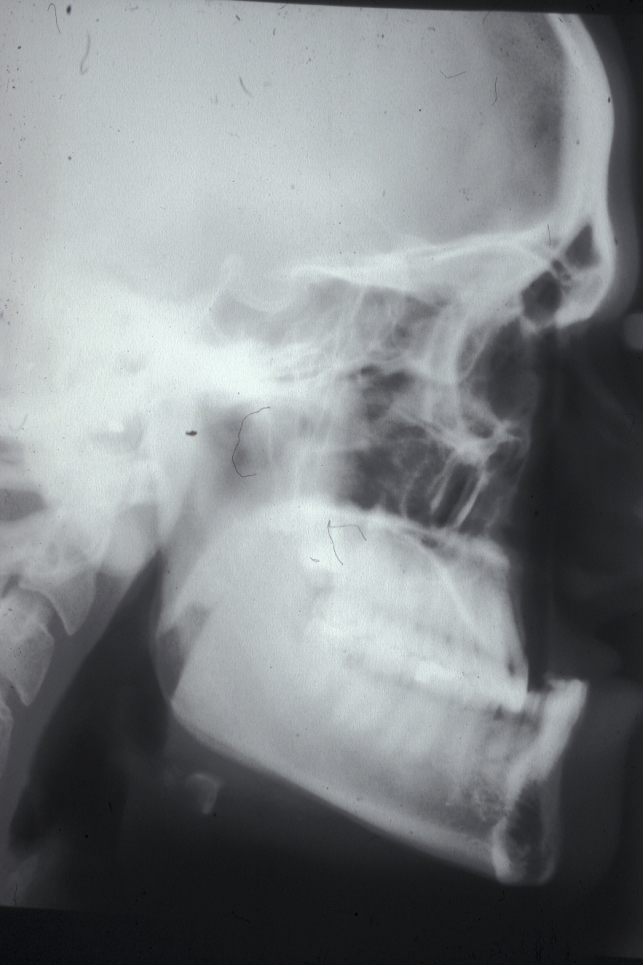

A lateral cephalogram (a profile side-view X-ray image of the skull and soft tissues) is required. This view supplements clinical analysis with cephalometric analysis (a range of measurements of the head and skull). See Figure 9 for an example of a lateral cephalogram.

Figure 9: A lateral cephalogram of a patient with a class III malocclusion.